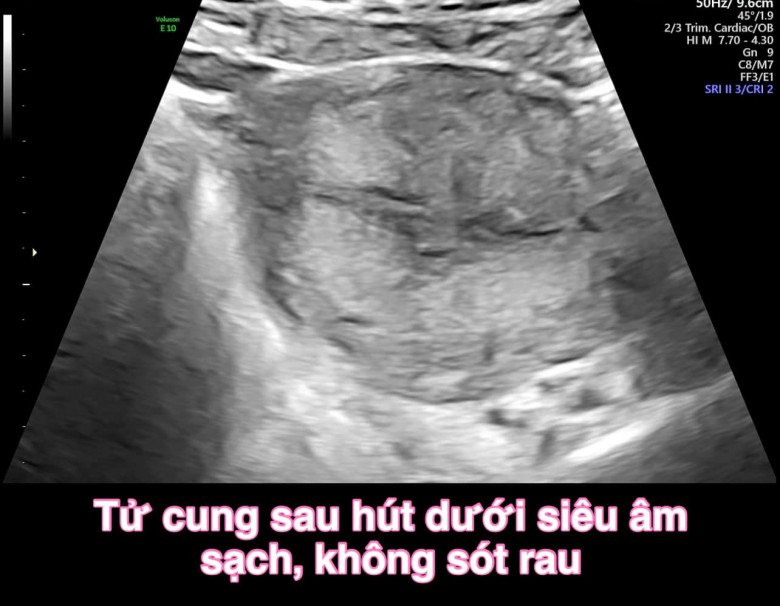

Xác định đây là trường hợp thai lưu nằm ở vị trí khó, uống thuốc và hút thai chân không đình chỉ thai nghén thông thường rất khó sạch, nhiều khi phải nạo mới sạch được nên bác sĩ Hùng đã cố gắng hút lại dưới siêu âm.

Bác sĩ đã cố gắng hút lại dưới siêu âm. (Ảnh: BSCC)

“Chúng tôi đã cố gắng hút thai lại dưới siêu âm, không nạo để ít tác dụng phụ nhất và cố gắng giữ buồng tử cung của bệnh nhân còn nguyên vẹn. Kết quả sau thủ thuật đúng như mong đợi, buồng tử cung sạch, không chảy máu hay tụ máu. Sau thủ thuật bệnh nhận được hướng dẫn uống kháng sinh và nội tiết chống dính buồng tử cung để đảm bảo sinh sản về sau”, bác sĩ Hùng nói.